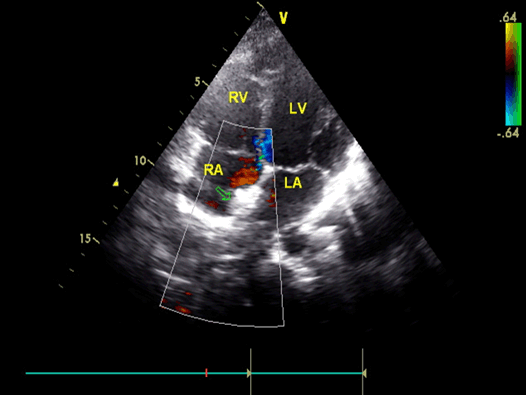

An ultrasound study of the vessels of the lower extremities revealed an intraluminal thrombus of the left superficial femoral and popliteal vein. A thoroughly detailed investigation of patient’s history revealed a minor sports related blunt injury of the left lower extremity a day before the initial symptoms, which was associated with lower extremities ultrasound findings. Additionally, an echocardiogram visualized a thrombus (2x1.5 cm) attached to the right atrium in conjunction with patent foramen ovale (Figure 5).

Figure 5 (A, B): Arrows indicate the location of the thrombus with its approximate dimensions.